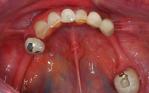

Replacement of all the teeth with an upper overdenture that clicks onto five implant fixtures and a fixed lower titanium framework acrylic bridge on four implant fixtures.

Before